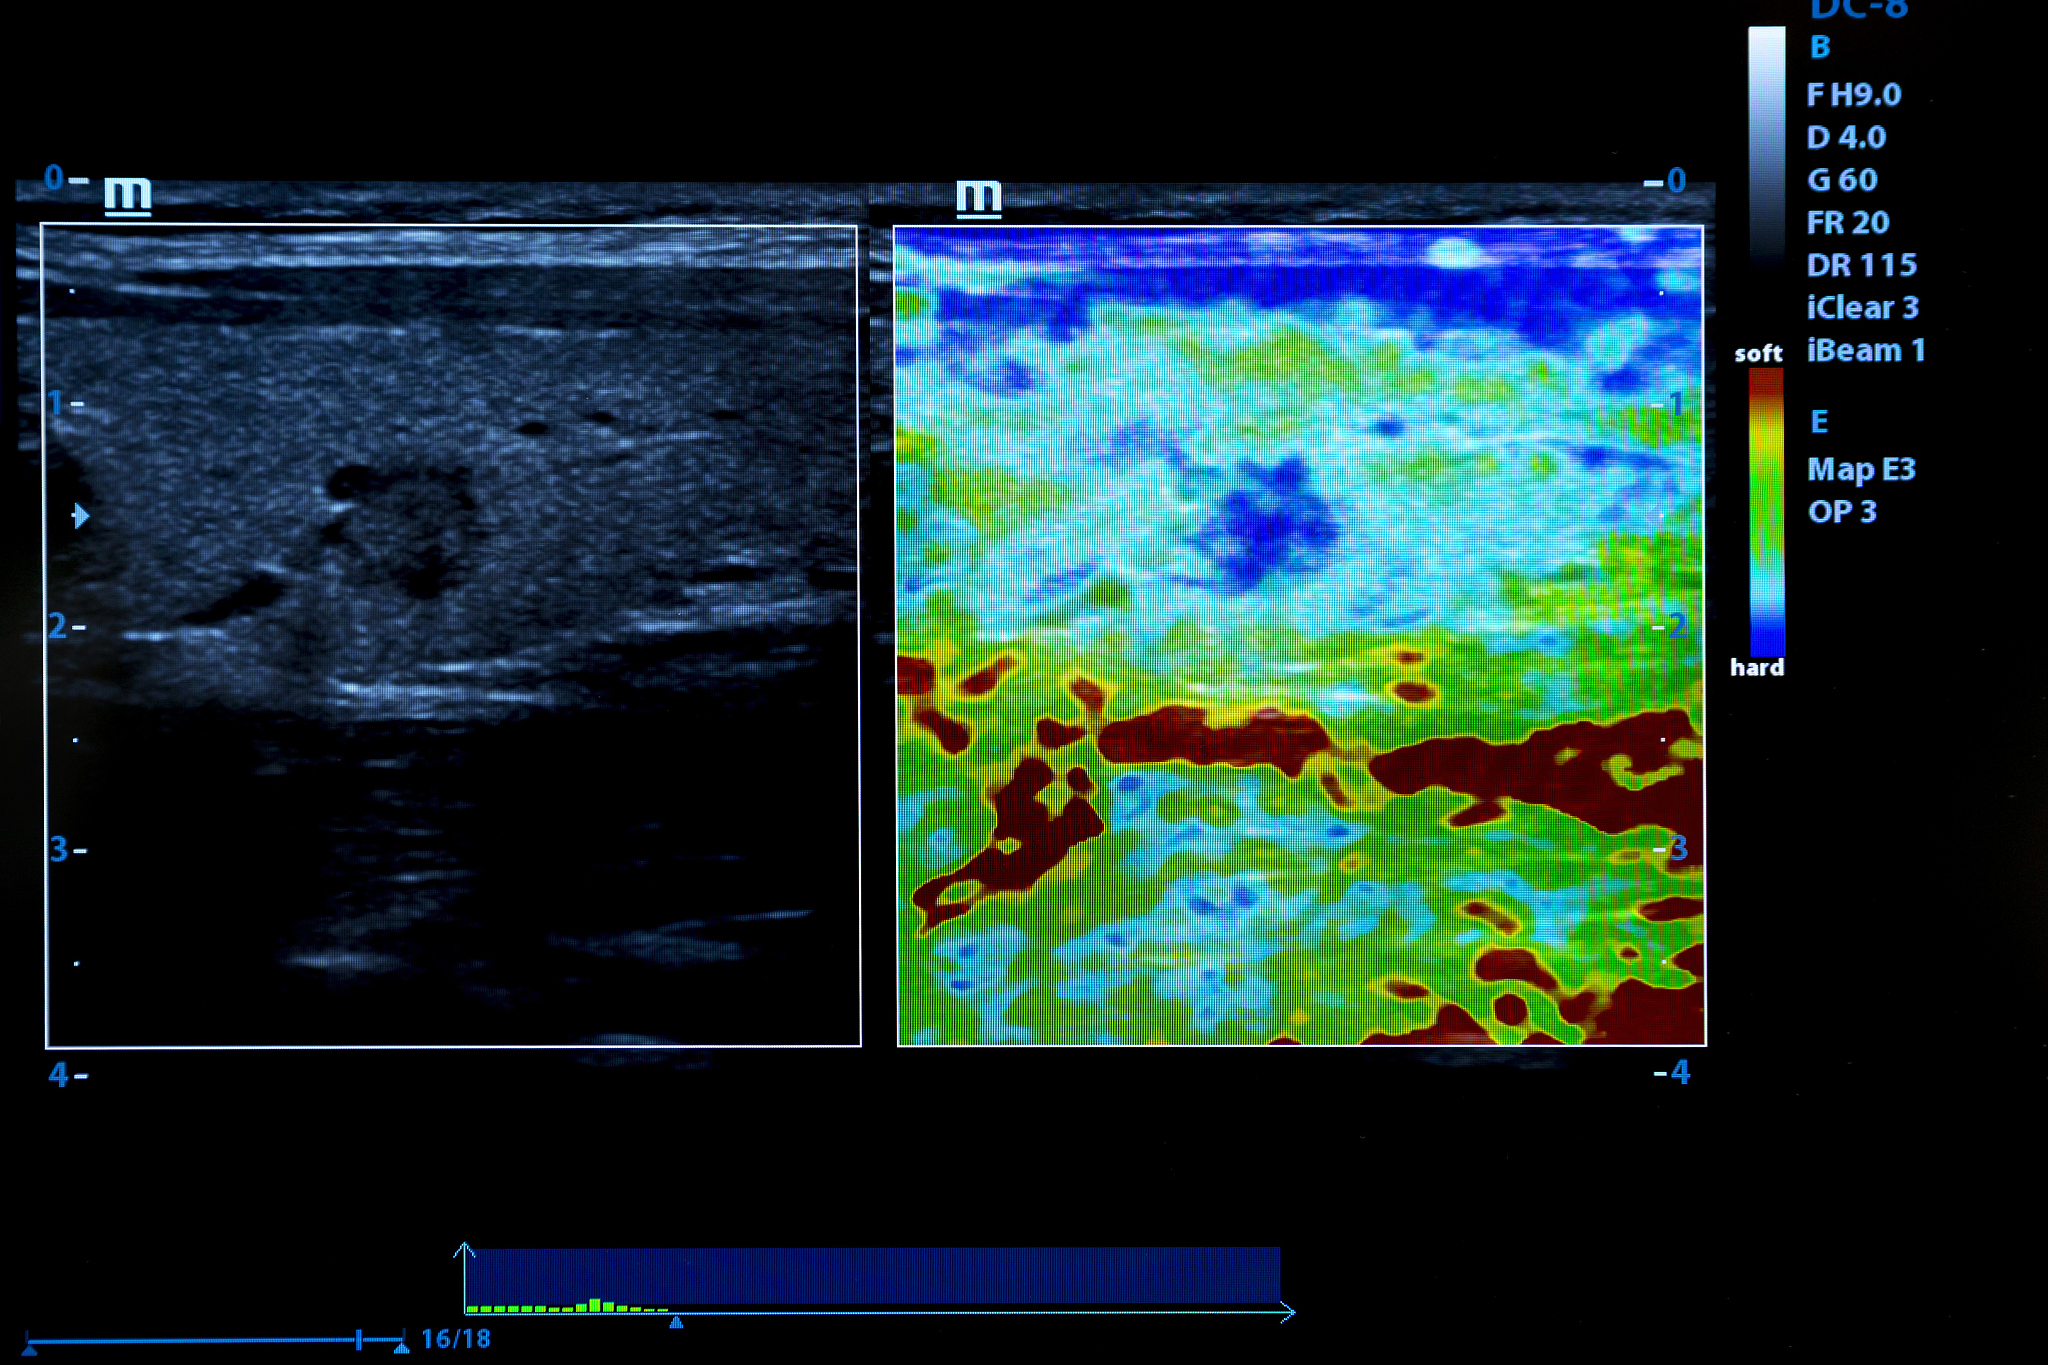

1. 分辨率问题:超声波的分辨率相对较低,无法清晰地显示细微结构和小的病变,尤其在深部组织中更为明显。

2. 噪声问题:超声成像过程中会产生一定的噪声,影响图像质量,尤其是在深部组织成像时噪声问题更为突出。

3. 深部组织成像问题:超声波在穿透深部组织时会受到散射和吸收的影响,导致成像质量下降,难以获得清晰的图像。

6. 高频超声成像问题:高频超声成像可以提高分辨率,但同时也会增加组织散射和吸收,影响成像质量。